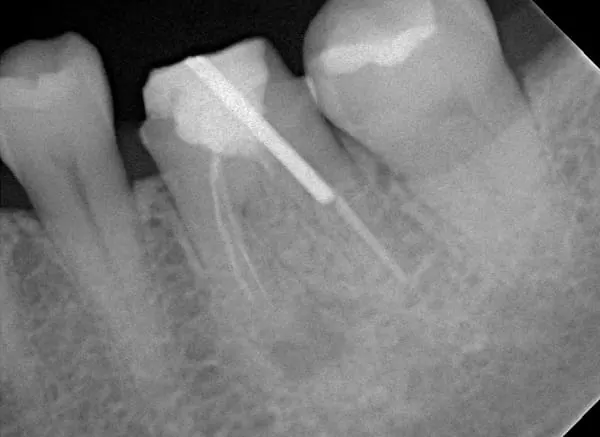

顯 微 根 管 治 療 後